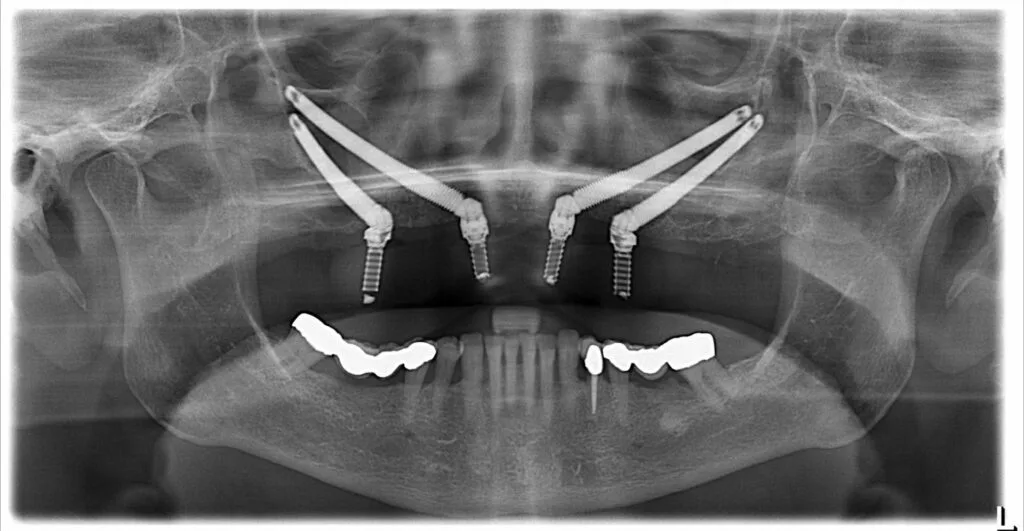

Gli impianti dentali zigomatici rappresentano una soluzione avanzata per i pazienti con grave perdita ossea nella mascella superiore. A differenza degli impianti tradizionali, che richiedono innesti ossei, questi impianti vengono ancorati nell’osso zigomatico (osso della guancia), offrendo una base solida e duratura per i denti protesici.

Gli impianti zigomatici sono impianti dentali avanzati ancorati nell’osso zigomatico (osso della guancia) per pazienti con grave perdita ossea della mascella.